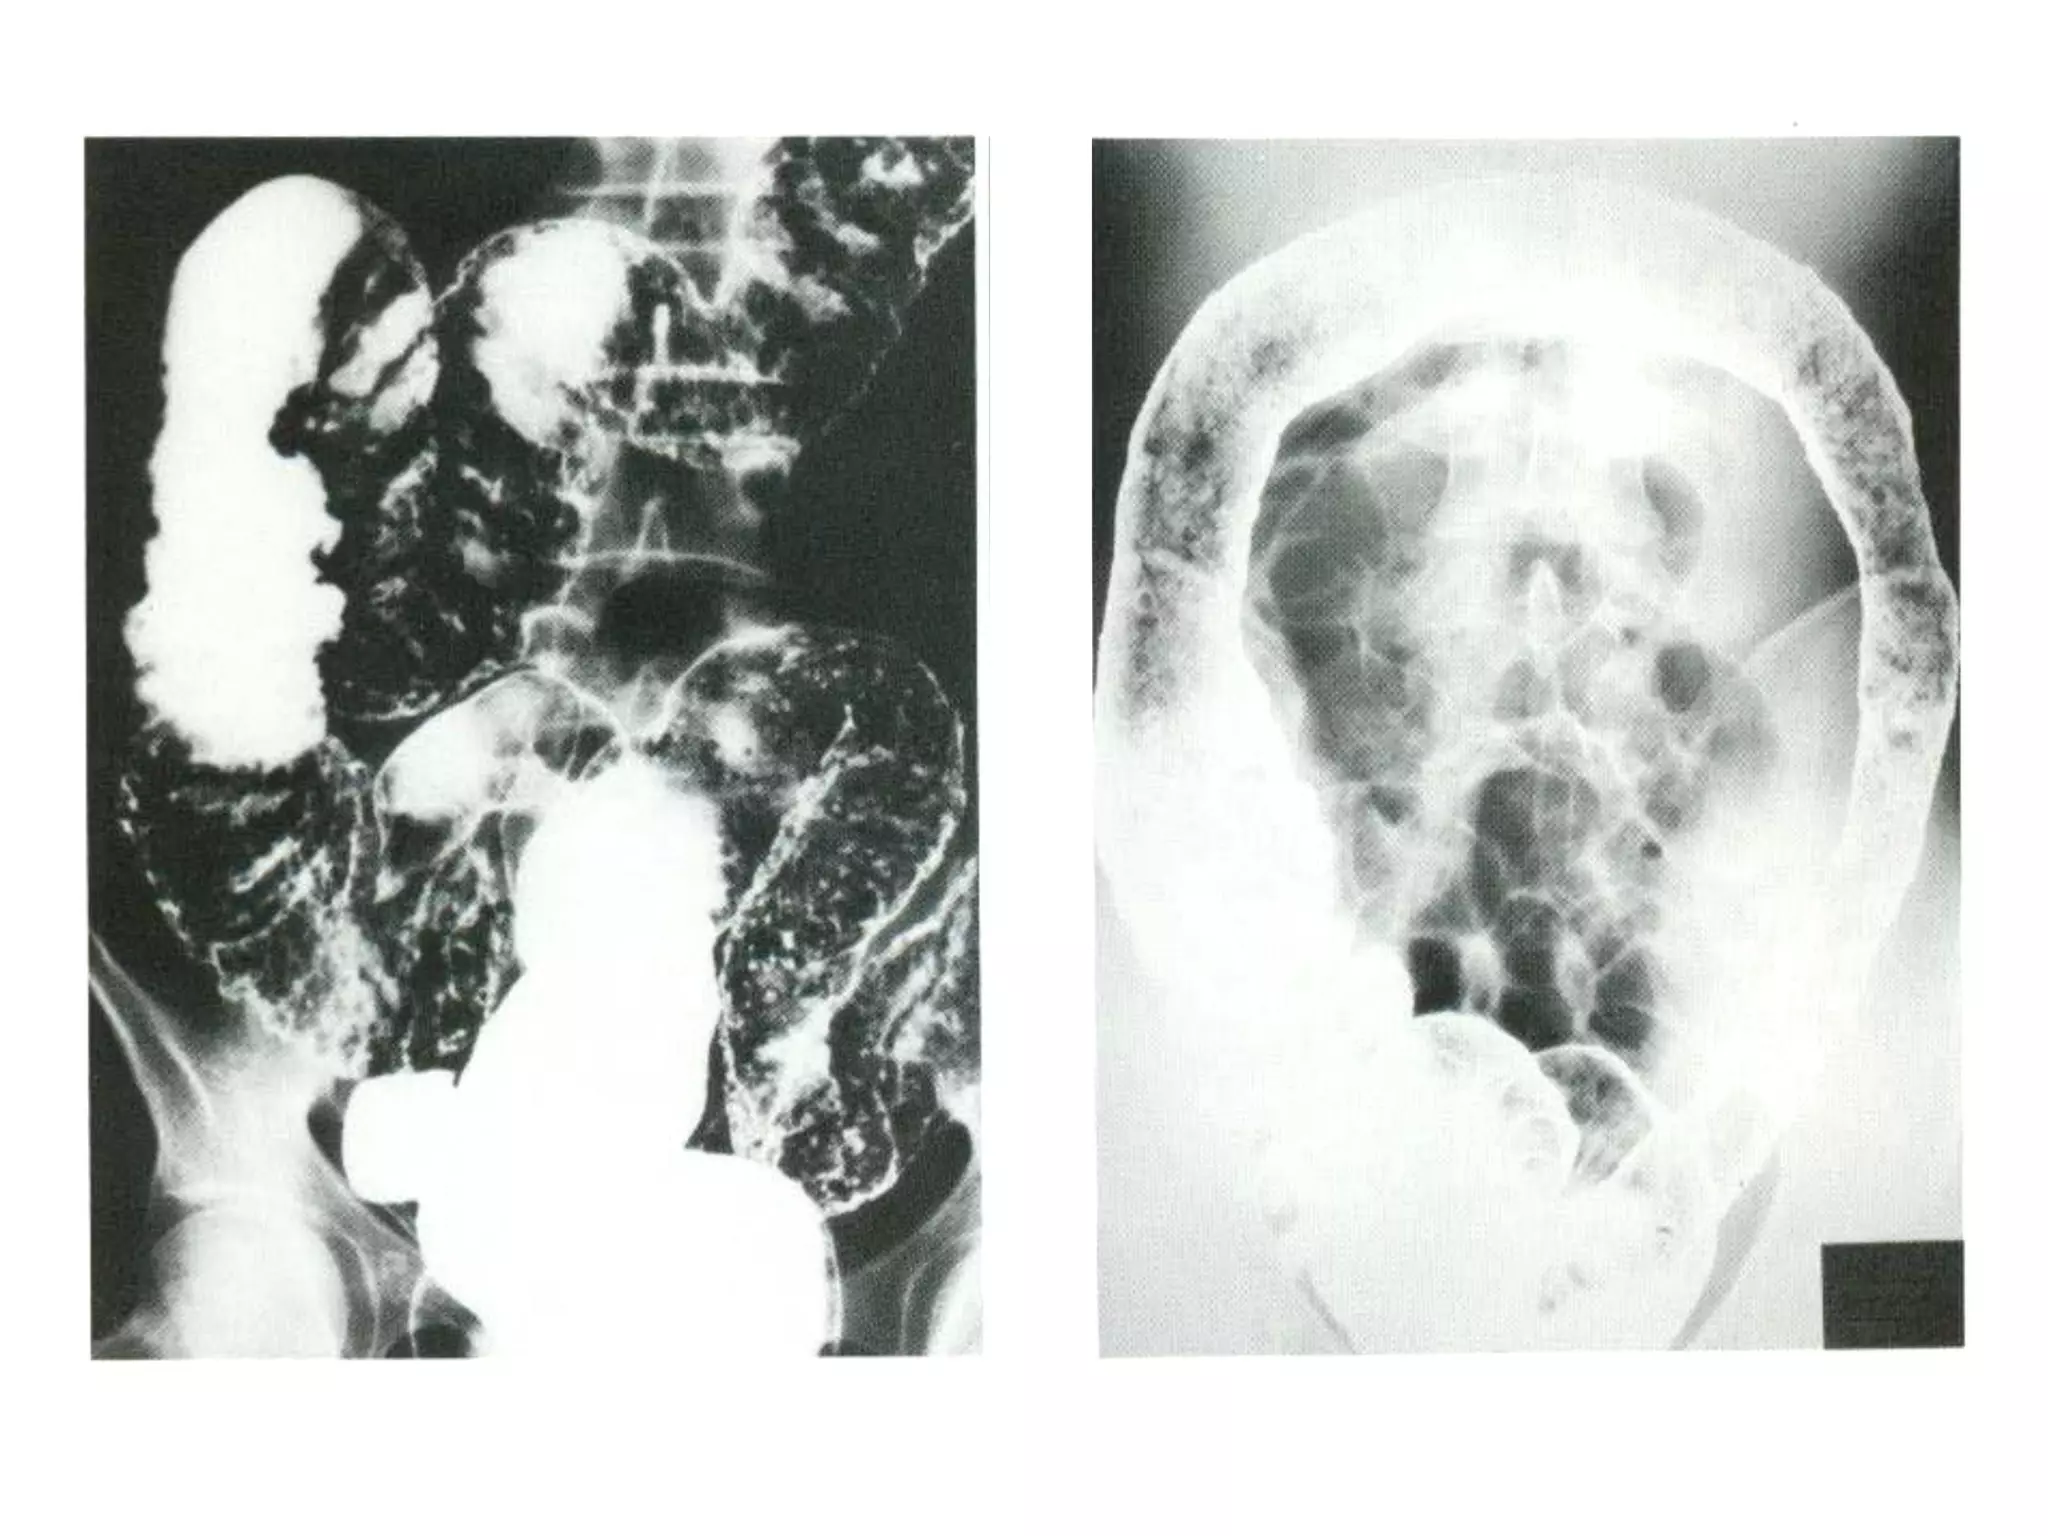

2. X quang:

 Tổn thương từng đoạn

 Không cân xứng

 Loét dạng đường dài, Loét dạng dao

(knife-like, transverse ulcers)

 Hình ảnh đá cuội trãi đường

 Hình thành đường dò

 Có tổn thương ruột non phối hợp

43